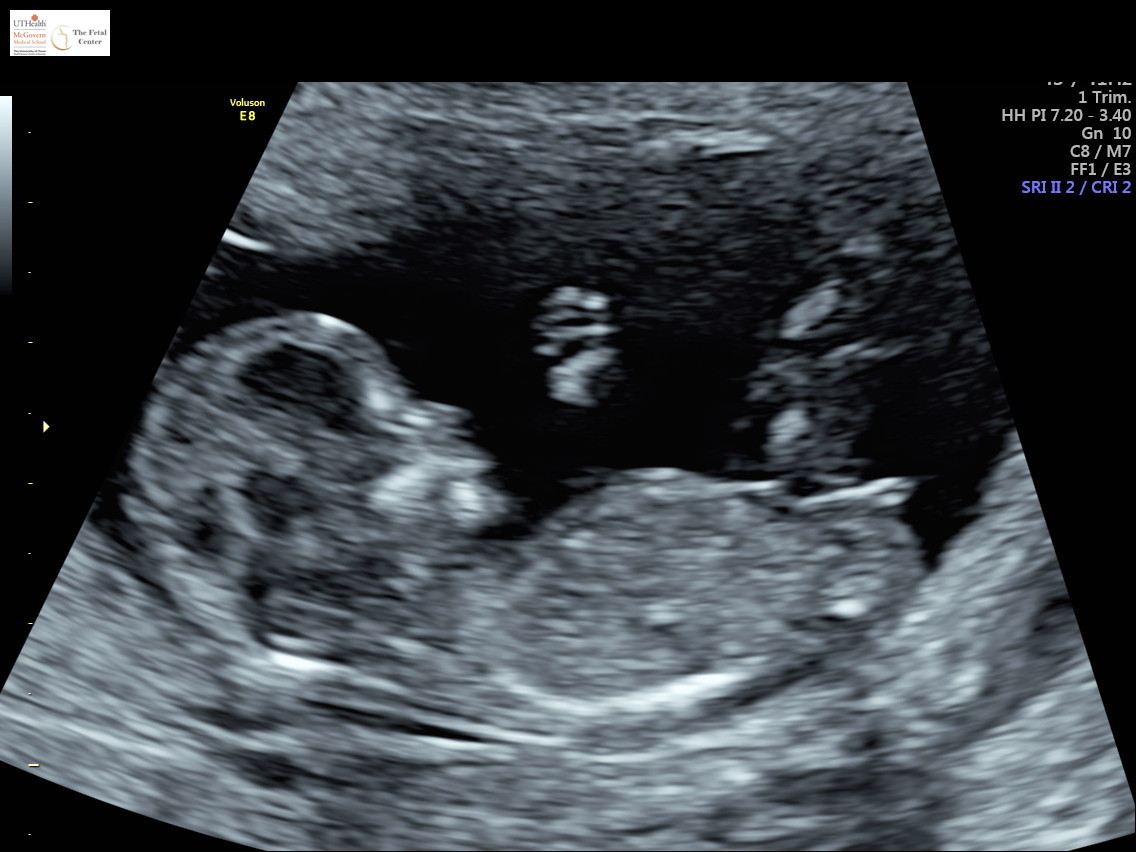

I AM SO FREAKING HAPPY FOR YOU SHENANIGANS! This has been such a long road, I know, but I am just absolutely thrilled you have your pink rainbow. :heart: